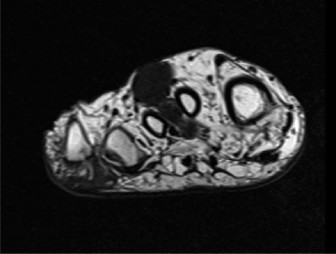

• ![Image](/media/upload/orthopedic-case-figure-2-64.jpg)

Figure 2: Intraoperative view during wide en bloc resection of a clear cell sarcoma from the foot. Note the careful dissection around the tumor, ensuring a generous cuff of normal tissue is maintained to achieve negative margins. The biopsy tract is also clearly visible within the resected specimen.